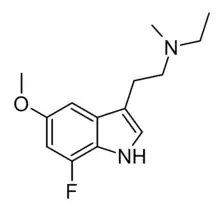

Substituted tryptamines, or serotonin analogues, are organic compounds which may be thought of as being derived from tryptamine itself. The molecular structures of all tryptamines contain an indole ring, joined to an amino (NH2) group via an ethyl (−CH2–CH2−) sidechain. In substituted tryptamines, the indole ring, sidechain, and/or amino group are modified by substituting another group for one of the hydrogen (H) atoms.

| Idalopirdine | artificial | 6-F | H | CH2C6H4(m-OCH2CF2CF2H) | 2-(6-Fluoro-1H-indol-3-yl)-N-(3-(2,2,3,3-tetrafluoropropoxy)benzyl)ethanamine | 467459-31-0 | |